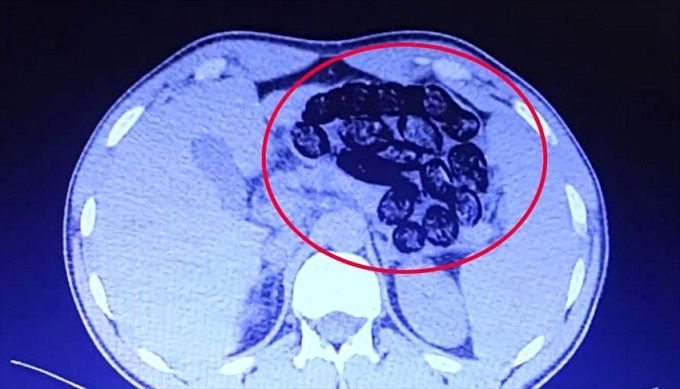

پلیس ترکیه دو شهروند ایرانی که ۹۲۰ گرم مواد مخدر را در قالب ۱۰۳ بسته در معده خود حمل می‌کردند تا از شهر وان به ازمیر بروند دستگیر کرد.

اداره امنیت استان وان ترکیه با انتشار اطلاعیه‌ای اعلام کرد پلیس این استان دو شهروند ایرانی که ۹۲۰ گرم مواد مخدر را در قالب ۱۰۳ بسته در معده خود حمل می‌کردند، دستگیر کرده است.

طبق اطلاعیه فوق٬ این شهروندان ایرانی قصد داشتند از فرودگاه فرید ملن شهر وان به ازمیر بروند که از سوی پلیس مبارزه با مواد مخدر شناسایی شده‌اند.

پلیس ترکیه پس از دستگیری این افراد، آنها را به بیمارستان منتقل کرده و ۹۲۰ گرم مواد مخدر موجود در معده آنها خارج شد.